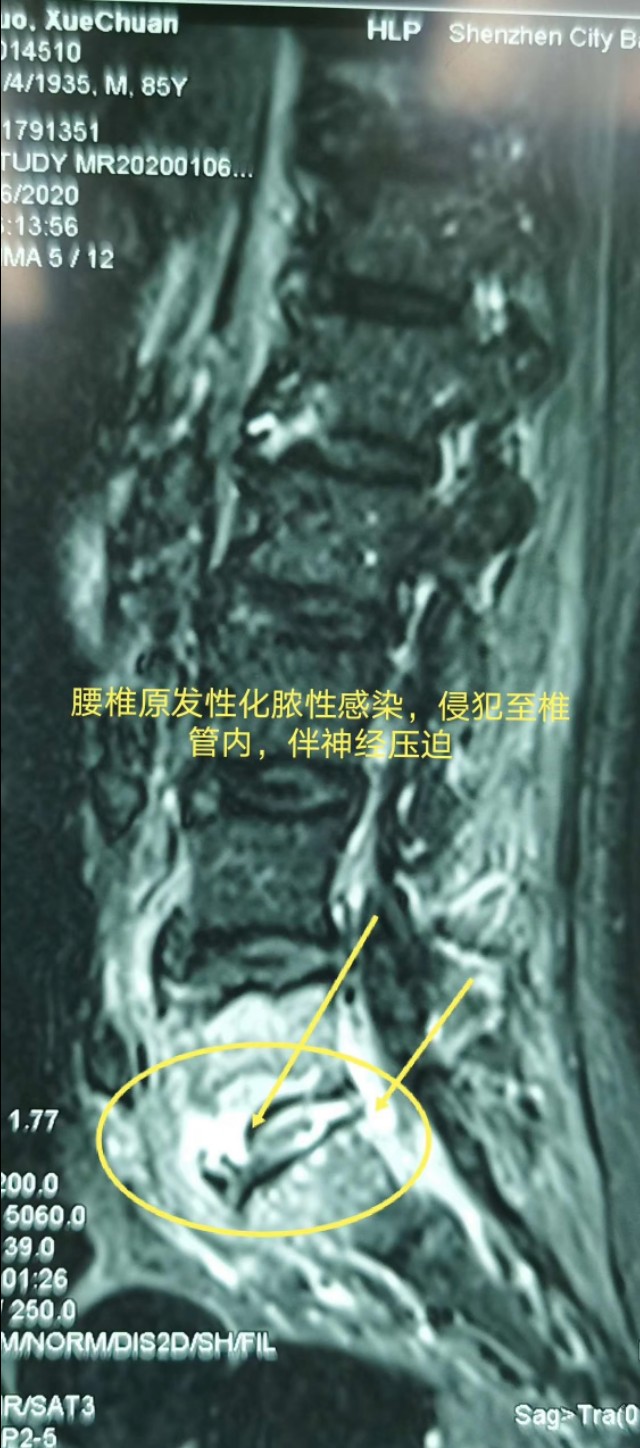

老人牙齿不好引起腰椎原发性腰5骶1化脓性感染,侵犯至椎管内,伴神经压迫。显微镜微创通道加导航辅助微创通道下间隙内感染清除,经微创入路行腰3腰4及导航下精准植入髂骨钉,钉道理想。深圳华大基因确诊细菌来源于牙齿������,术后一个月复查,病人己完全康复������